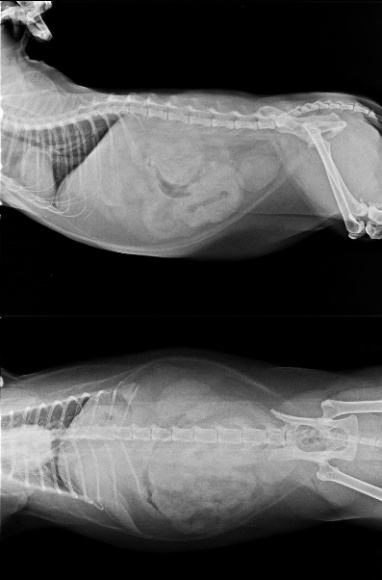

主題: 腸道淋巴癌的憨面 申請者姓名: 臺北市支持流浪貓絕育計劃協會 花色: 申請日期: 2015-04-28 14:13:00 申請者部落格: 申請者臉書網址: 所在縣市/合作醫院: 台北市/極光動物醫院 治療費用: 59679元 需求人數: 63人 已結案 (2022-03-11 00:08:43) 報名人員: dindinape(已付款)、Patrick、Patrick、玥青(已付款)、Lisa(已付款)、Kristy Lee(已付款)、黑踏(已付款)、林子婷(已付款)、許芯芯(已付款)、Annisui Strauss(已付款)、Manson Liu(已付款)、李 其展(已付款)、Jodie(已付款)、selina(已付款)、張雅筑、Juoshi Wu(已付款)、陳哈君(已付款)、Peggy Ho(已付款)、陳小茜(已付款)、Becca Huang(已付款)、陳小茜(已付款)、Cathy Wang(已付款)、咪咪靜(已付款)、Kitty Chen(已付款)、張阿毛、Jackie Kang(已付款)、Daniel Tsai x2(已付款)、Shizuka Ho(已付款)、Elin Kwo、watermama(已付款)、Mickey Han(已付款)、vigia(已付款)、謝佩芳(已付款)、Sunny Chen(已付款)、Penny Deng(已付款)、丁丁 x3(已付款)、Carol Kuo x2(已付款)、Lily Wu x2(已付款)、Tinas(已付款)、Bobbie Chen(已付款)、Ken Lee x2(已付款)、Ken Lee x2、Yijun Deng(已付款)、amency(已付款)、廖文琳(已付款)、千葉狐(已付款)、小琪(已付款)、Elin Kwo、Elin Kwo(已付款)、vivian(已付款)、Hui Hui Ting x3(已付款)、林小豬(已付款)、a-song(已付款)、千娌、hakumaio(已付款)、陳 小豬(已付款)、Vivi(已付款)、week0207(已付款)、Cherry Wang(已付款)、Cynthia Chen(已付款)、lavinia x2(已付款)、Joe Chen(已付款)、 候補人員: 動物病情說明: 4/14憨面精神食慾變差,就診超音波和X光檢查發現腸道有4.5公分的團塊,需要緊急開腹探勘,有可能是腸道腫瘤,但目前比較棘手的是,憨面血容比往下掉,目前17,急需要輸血,帶安養之家的的白居易、黑格爾、奶油獅前往比對,所幸白居易配上抽血50CC,4/15一早進行手術,開腹後發現腸道上腫塊極有可能是惡性腫瘤,進行腸切除腸吻合手術,並將腫塊送組織病理檢驗和細菌培養,憨面兒住院心情很布魯,不太吃東西,因腸道切除術後只能吃泥狀物質,志工探望一口口慢慢的餵了兩條肉泥,他很勉強但至少願意吃,血溶比往下掉一點,希望能回穩,憨面兒加油,你要努力,才能早點回家!

4/15親愛的憨面兒今日血有上升一個百分點,但是還是沒心情主動進食,用手餵他,還勉強會舔,寶貝要乖乖吃飯,好一點兒就可以回協會唷!

4/16晚上去看憨面,醫生說他今天已願意自己進食了!

由於腸子長了不明組織,這次除了割掉那團不明增生腫塊,也切除部份腸子,

說明憨面未來飲食得嚴加限制,他必需與最愛的乾乾和零食餅乾告別一陣子,

希望切片化驗結果不要太糟,好消息是他今日血溶比上升4個百分比,

已到達22 ,繼續維持下去 就可以回協會休養囉!

4/20憨面出院了,他很開心可以回家,我們也一樣!

但,壞消息是切片報告,憨面證實罹患淋巴癌,

我們一起快樂過日子與抗癌吧!